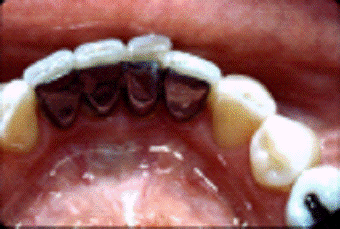

Интракоронковое шинирование. Этот

вид шинирования используется во фронтальной и жевательной группе зубов.

Шина покрывается композитным

материалом в тон зуба.

Для интракоронкого шинирования

применяется арматура на основе не органической матрицы. Стекловолокна имеют

лучшую биосовместимость с тканями человеческого организма, так как состоят из

биоинертного стекла, а не из пластика. Она (арматура на основе не органической

матрицы) не требует специальных условий хранения, легко режется обычными

ножницами, хорошо адаптируется ко всем поверхностям зубного ряда. Выпускают ее

модификацию в виде полого жгутика, что значительно расширяет сферу применения.

Жгутик оптимален для шинирования жевательной группы зубов с использованием

техники создания бороздки, для восстановления одиночного дефекта зубного ряда

или в качестве альтернативы внутрикорневым штифтам.

Недостатки интракоронкового

шинирования:

. Риск при препарирование

твердых тканей зуба

. Возможно развитие кариеса

под шиной, затруднение гигиены полости рта

. Возможен разрыв шины и\или

скол материала.

. Нарушение фонетики из-за

объема шины.